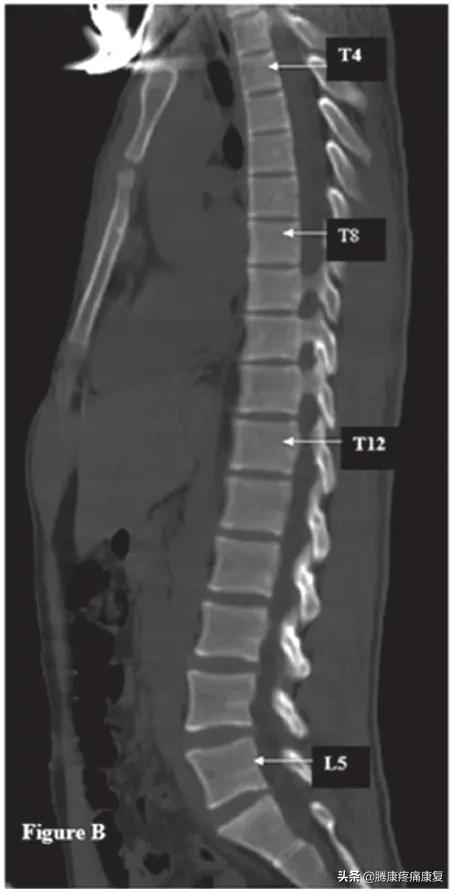

对脊柱的X射线成像可以显示出脊柱的矢状面排列。

平背表明脊柱失去了正常的生理曲线,正常情况下当我们从侧面观察身体时,矢状轴与垂直方向的对齐不应该超过5MM,而平背综合征的患者,由于重心前移,轴心距垂直距离会超过5MM。